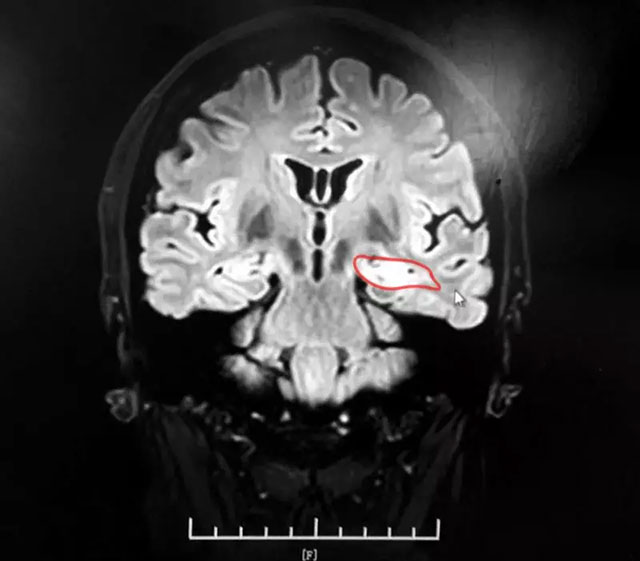

▲ 患者左侧海马病灶区

为了确定患者是否患有癫痫病,在入院的第一天苏女士就做了脑电图检查,但检查结果却差强人意,和患者第一次脑电图检查结果一样,并未发现患者任何异常情况;随后患者又进行了头颅MR检查,检查提示患者左侧海马异常。为了进一步明确病因,戴主任建议患者进行MR海马增强扫描:MRI平扫+MRS+MRSI,影像提示:1、患者左侧海马信号增高;2、MRS 双侧海马Cho峰稍升高(左侧NAA/Cr+Cho=0.42;右侧NAA/Cr+Cho=0.52),结合临床,以及检查结果,戴主任认为患者患癫痫病的几率非常大。